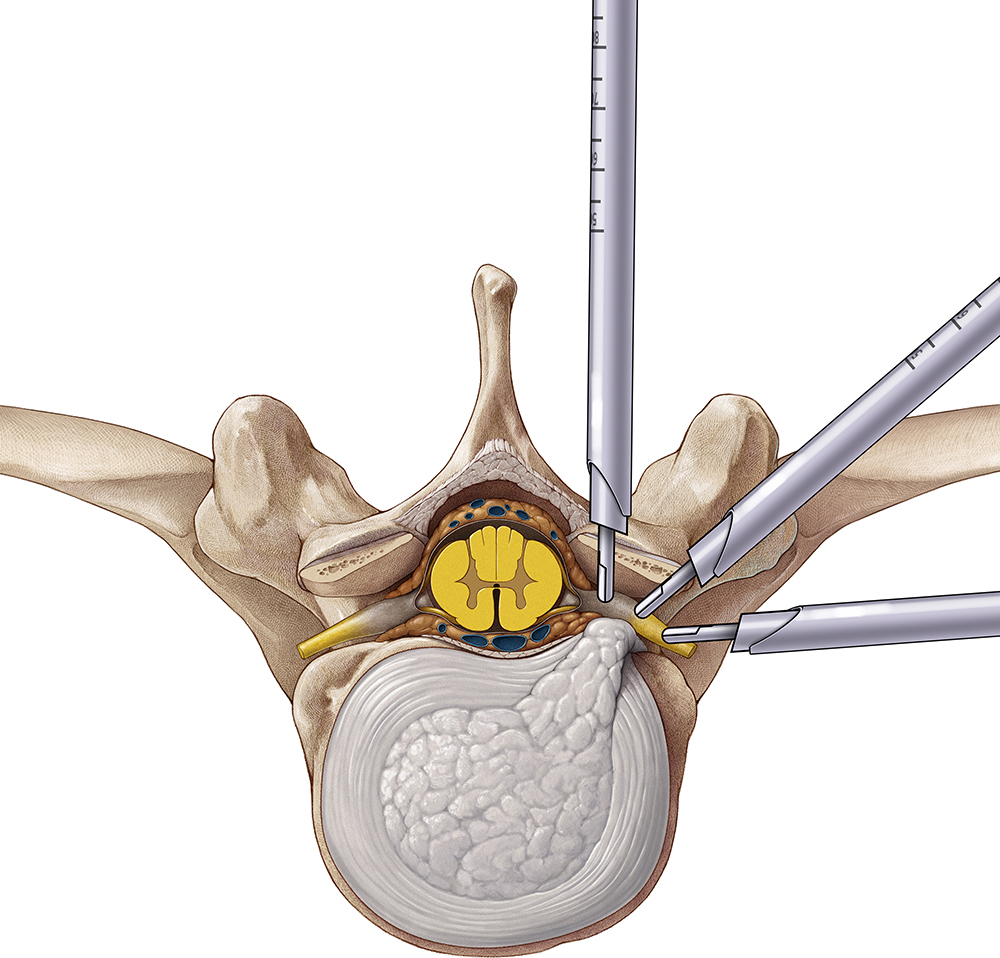

– Microdiscectomia: consiste em retirar o fragmento de disco herniado com auxílio de algum aparelho óptico, como lupas cirúrgicas ou microscópios.

– Discectomia endoscópica: consiste em retirar o fragmento de disco herniado com auxílio de um endoscópio, também pode ser usado para aumentar o espaço do canal vertebral e do forâmen acometido.

– Laminectomia: para remover estruturas ósseas ao redor de uma hérnia e expandir o canal vertebral.